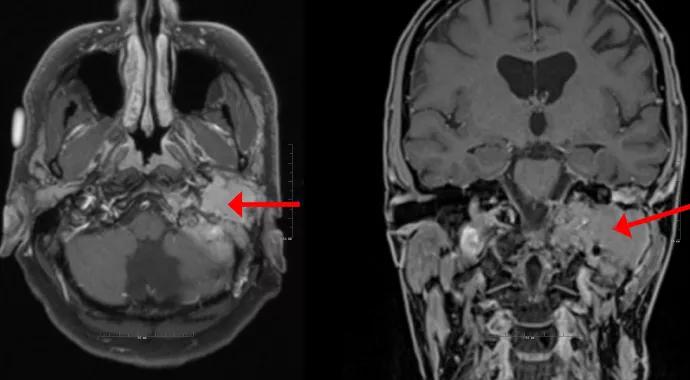

Many centers, including Cleveland Clinic, are offering patients partial tumor resections to reduce symptom severity and to improve functional outcomes. The images that accompany this article are from a patient who was diagnosed with a massive recurrence of a previously resected tumor. The tumor was too large to allow for radiosurgery, and the patient had synchronous lesions, including an ipsilateral vestibular schwannoma and a cholesteatoma in the closed-off ear and mastoid cavity (Figure 1). The patient underwent resection of most of the tumor bulk, but some residual tumor was left in the pars nervosa so that the integrity of the lower cranial nerves was not compromised (Figure 2). Radiosurgery can be performed at a later date to control the growth of the much smaller tumor remnant if the need arises.

Figure 1. Axial (left) and coronal (right) MRIs show a massive recurrent left glomus jugulare tumor (arrows) involving the petrous apex and the posterior fossa dura in a previously operated ear. During the patient’s previous surgery, the facial nerve was rerouted at the geniculate ganglion, and the ear canal was oversewn. Not shown is a labyrinthine fistula from the epidermoid cholesteatoma lateral to the glomus tumor and a synchronous intracanalicular vestibular schwannoma in the same ear.